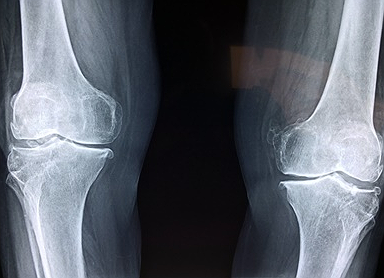

안녕하세요. 클릭 궁금해결소 입니다. 오늘은 관절염과 관절통증 개선에 효과적인 종근당 이모튼 캡슐에 대한 정보를 낱낱이 파헤쳐보도록 하겠습니다. 그동안 관절 불편한 증상으로 인해 고생하셨나요? 그렇다면 잘 오셨습니다. 아래에서 여러분의 지긋지긋한 관절염과 통증개선에 도움이 될만한 정보를 얻어가시기 바랍니다. 구체적인 사항이 궁금하시다면 아래를 참조하세요.

종근당 이모튼 캡슐의 효능은 크게 두가지가 있습니다. 퇴행성 관절염을 포함한 골관절염에 효과가 있습니다. 그리고 치주질환에도 도움이 됩니다. 치주질환으로 발생한 출혈과 통증을 제어하기 위한 보조적인 요법으로 활용될 수 있습니다. 그렇다면 종근당 이모튼 캡슐은 어떻게 복용해야 안전할까요? 다음을 참고하세요.